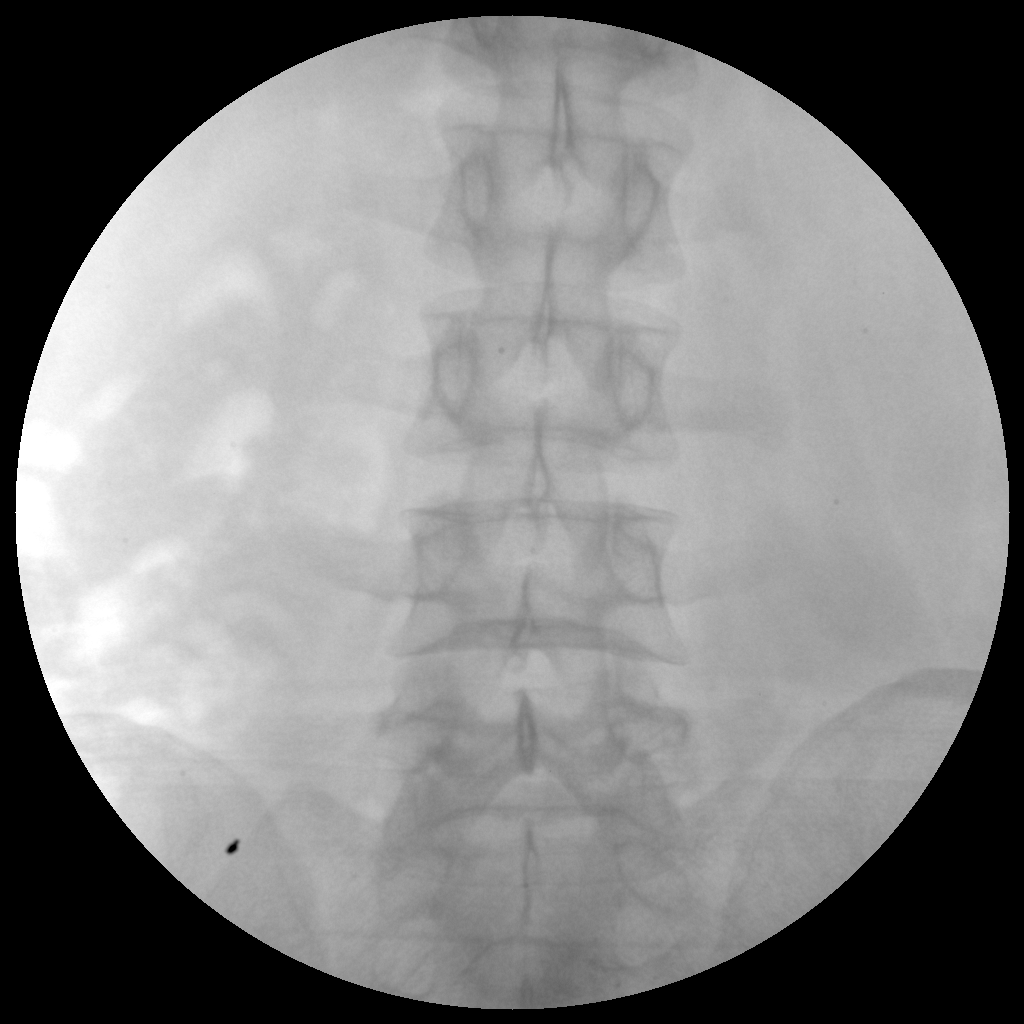

PLX112B 系列高频移动式手术X射线机

●经典影像工作站,可隔室操作避免辐射●全数字化百万像素影像系统,图像清晰●灵活的C臂机架设计,满足临床大范围运动●临床功能丰富,具备脉冲控制、数字摄影、自动透视等●具备手持控制器,远离主机也可自由控制